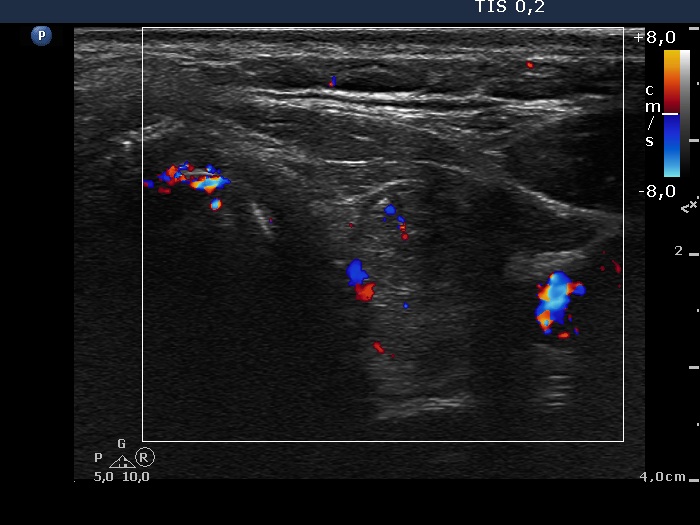

Right lobe, longitudinal scan

Left lobe, transverse scan, color Doppler mode. The vascularization is not specific.